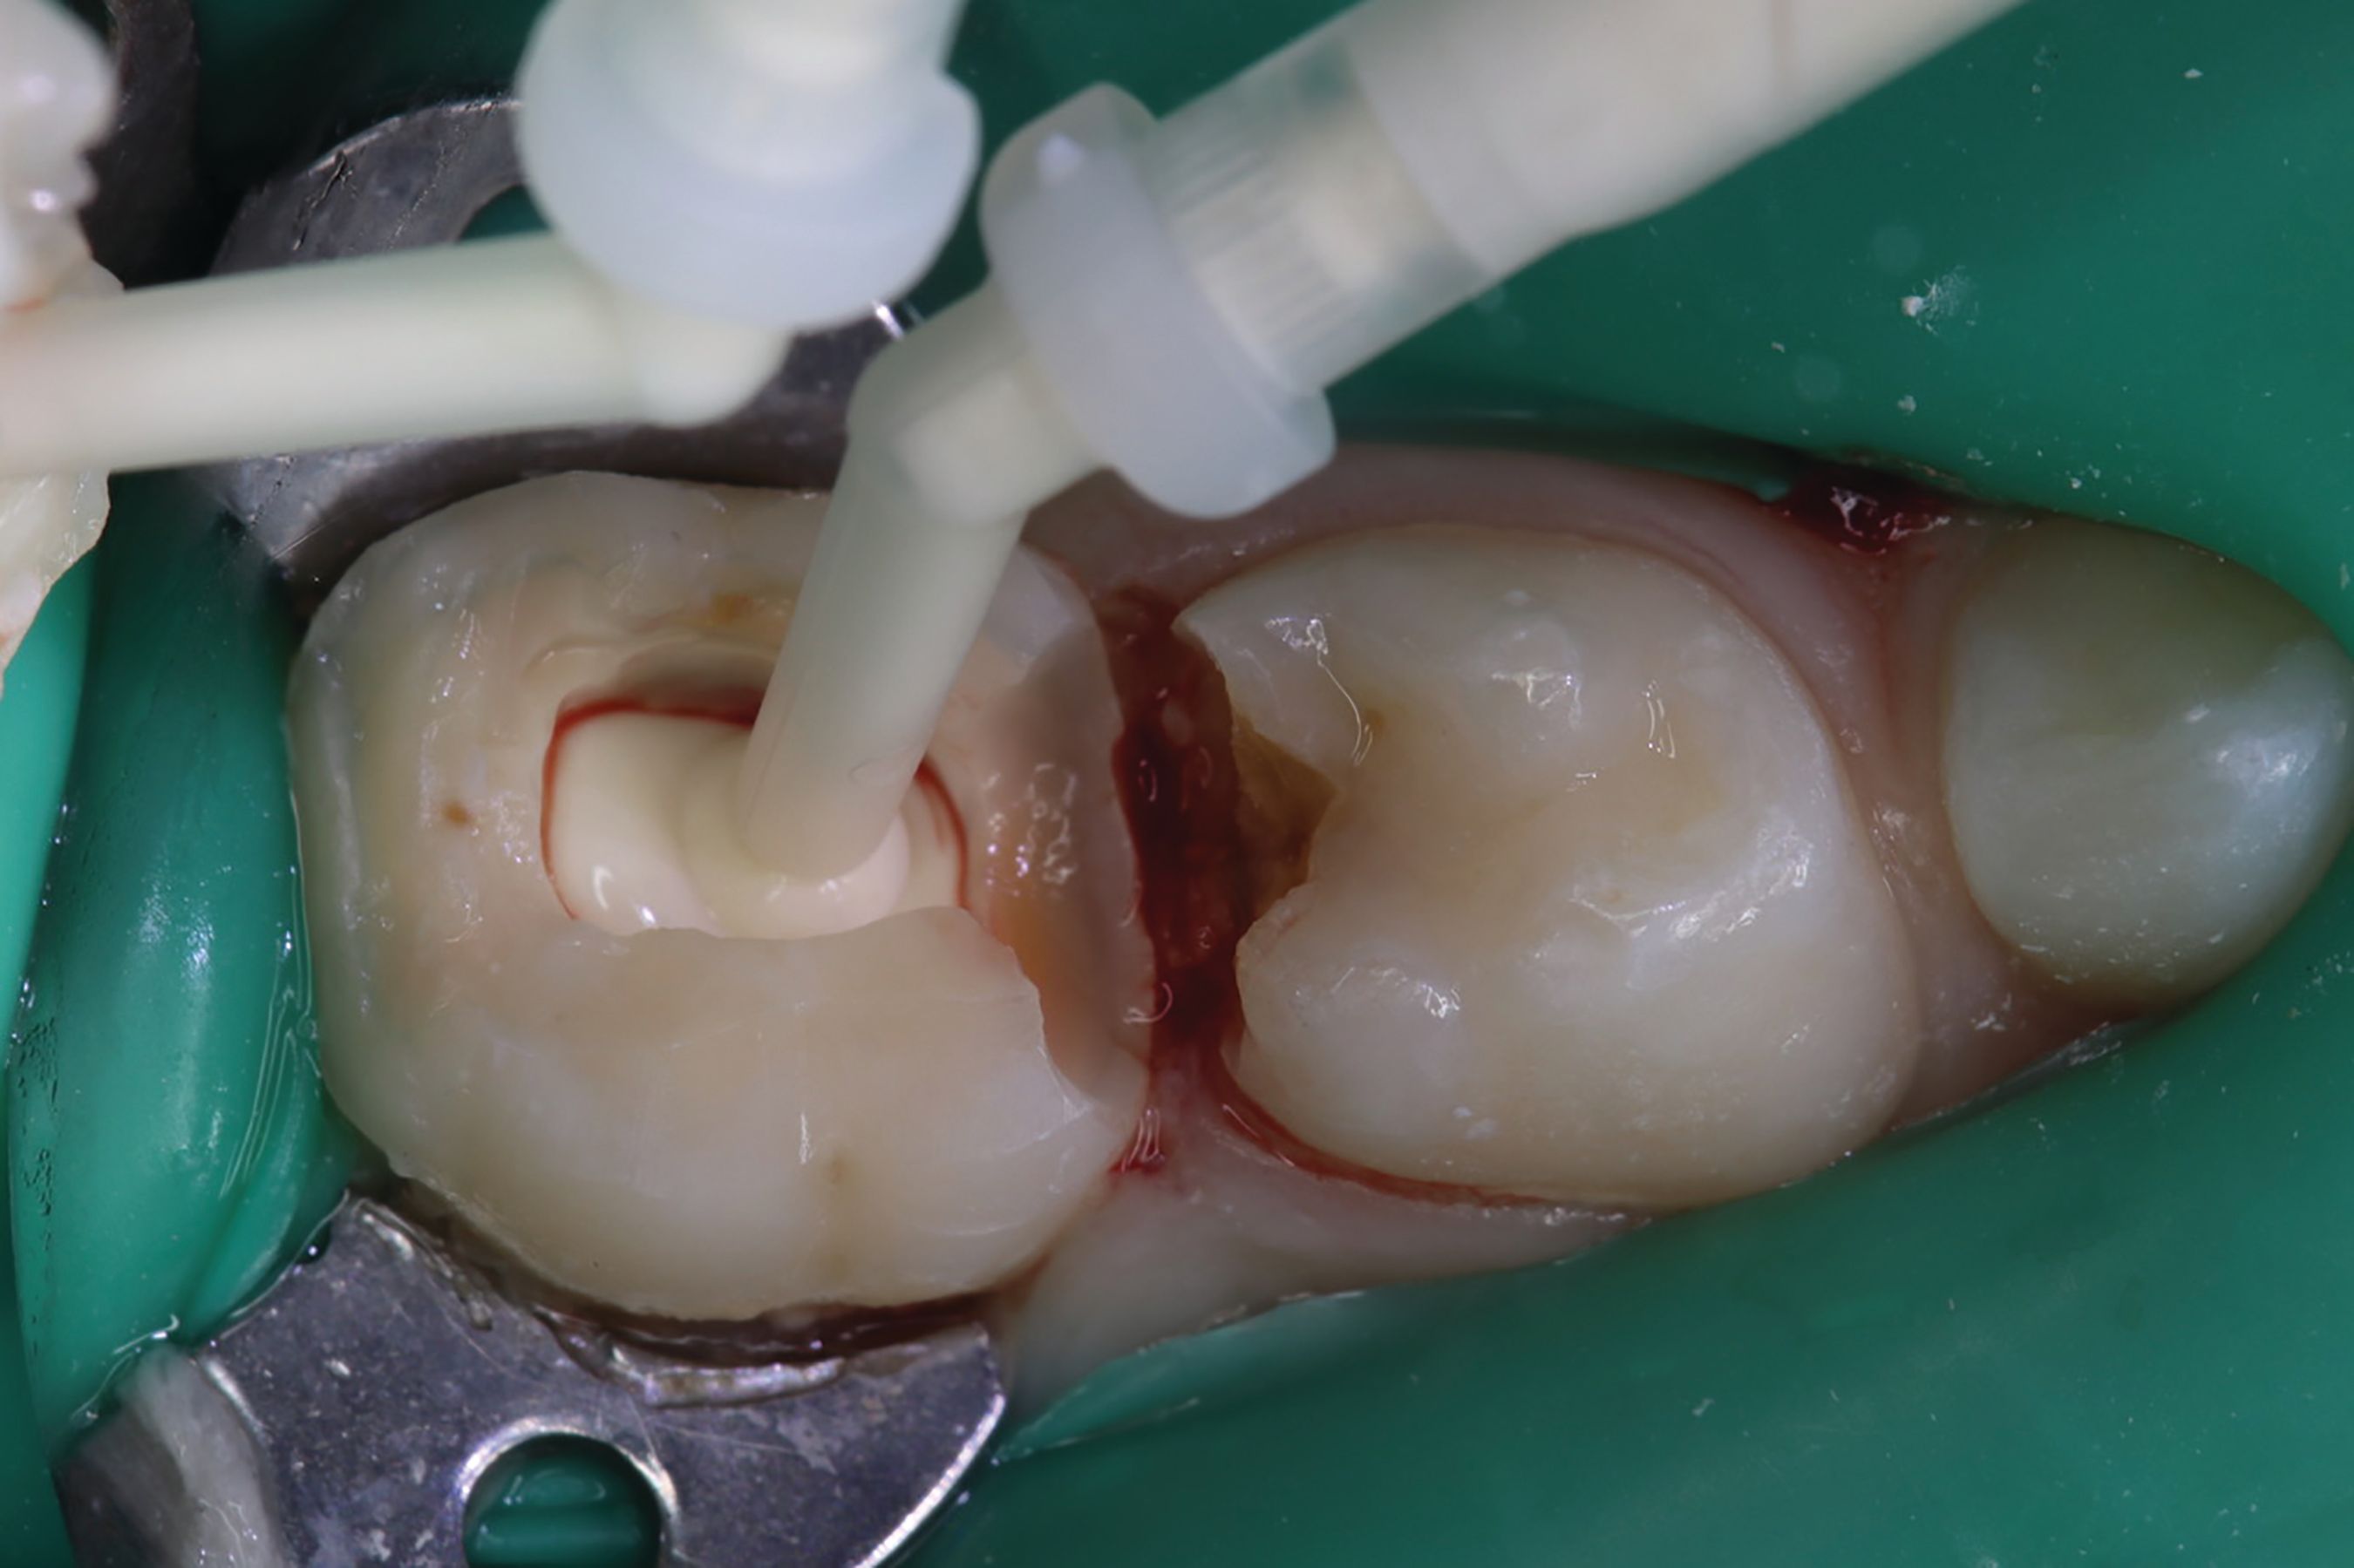

Amputation of coronal pulp chamber to the level of radicular pulp stumps was performed with NSK Dental slow speed large round bur #8, removing coronal pulp tissue with gentle upward motion (Fig. 2). Hemostasis is achieved with a saline-soaked sterile cotton pellet (Figs. 3-4). Figure 5 also illustrates hemostasis.

Fig. 4

[ Figs. 1-9 ] Pre-operative view-primary second molar requiring pulpotomy procedure (Fig. 1). Amputation of coronal pulp chamber to level of radicular pulp stumps with NSK Dental’s slow speed large round bur #8, removing coronal pulp tissue with gentle upward motion (Fig. 2). Hemostasis achieved with saline-soaked sterile cotton pellet (Figs. 3 & 4). Hemostasis achieved (Fig. 5). Extrusion of TheraCal PT into pulp chamber, being sure to reach base of coronal pulp chamber with material and without voids or bubbles and light cure (Figs. 6 & 7). Cured TheraCal PT (Fig. 8). Full-coverage stainless-steel crown (Fig. 9).